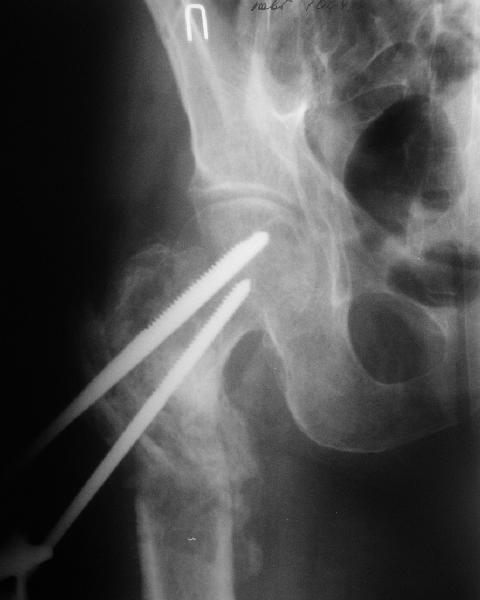

В приложении пример пациента, близкого по картине к тому, что представил Виктор (варус и смещение периферического отломка на поперечник кзади). Сделали как раз то, что Виктор исходно намеревался - аппаратная коррекция и затем гамма.